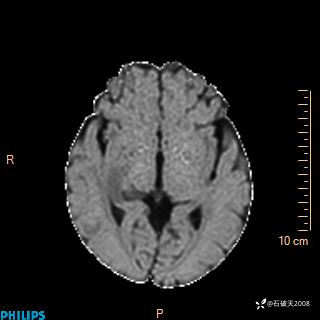

T1

FILAR